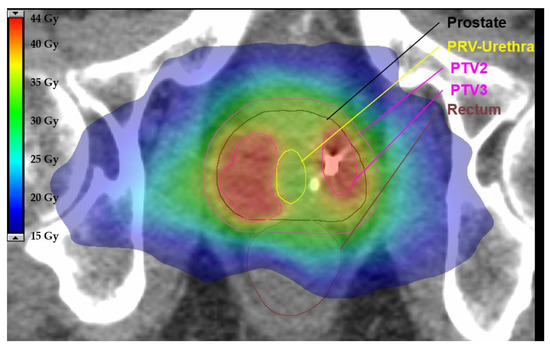

For the experimental arm (SBRT) PTV1 is created by the addition of CTV1 and CTV_SV and 4 mm isotropic expansion (see Figure 1a,b). PTV 2 is created by 4 mm isotropic expansion of CTV 1 (see Figure 1c). PTV3 is created by 0–2 mm isotropic expansion of GTV-union. PTV3 must not overlap with the PRV-Rectum, PRV-Rectum_adapt, Bladder or PRV-Urethra contours. In this case, the overlapping volume must be removed from PTV3 even if parts of the GTV are excluded (Figure 2a–c).

Figure 2.

Definition of PTV3 for SBRT. Planning target volume 3 (PTV3) is created by of 0–2mm isotropic extension of the gross tumour volume (GTV) (a,b). Overlapping parts with planning organ at risk volume (PRV) of rectum and urethra are removed from PTV3 (c).

For the definition of PTV3, the GTV-union (Figure 3, a, green), merged by using all delineated GTVs, is extended by an isotropic margin of 0–2 mm (b). Organs at risk (OARs) are delineated (a): bladder (yellow), urethra (dark yellow), rectum (orange/brown) and respective PRVs are created by isotropic expansion of 2 mm (b). The PTV-volume, overlapping with the PRV of either rectum or urethra, must be deleted from PTV3 even if parts of the GTV are excluded (c).

Figure 3.

Exemplary axial slide of a representative plan using stereotactic body radiotherapy (SBRT) for the experimental arm. This example demonstrates how overlapping parts between the planning target volume (PTV) and planning organ at risk volume (PRV) are removed to define the final PTV. There is a steep dose gradient to spare the urethra while preserving a sufficient dose to the PTV. Relevant organ as risks, PTVs and isodoses in colorwash are illustrated according to the legend.

Prescription doses for the PTVs and constraints for OARs in the experimental arm (SBRT) are provided in Table 2 and Table 3 [7,32,52,53,54]. Prescription doses for the entire prostate must be calculated in subtraction volumes of the PTV and the Boost-PTV (PTV3). Prescription doses are the following: For PTV1 (subtraction: PTV1–PTV3): 30 Gy in 6 Gy per fraction, and for PTV2 (subtraction: PTV2–PTV3) 35 Gy in 7 Gy per fraction. The prescription dose for PTV3 ranges between 40 and 42 Gy (see Figure 3). Initial planning should be performed with a prescription dose of 42 Gy and should be reduced up to 40 Gy in 1 Gy intervals when dose constraints are not met. In cases of large boost volumes (≥10 mL and/or ≥1/3 of the prostate), the dose to PTV3 must be restrained to 40 Gy in 8 Gy per fraction.